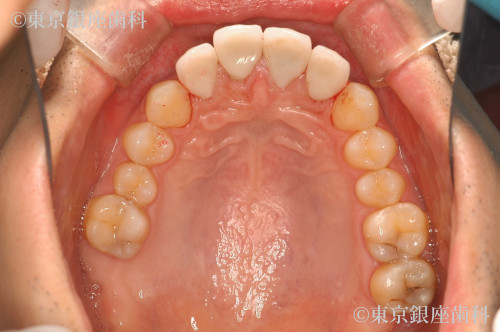

ひどい虫歯で歯がボロボロ

Before